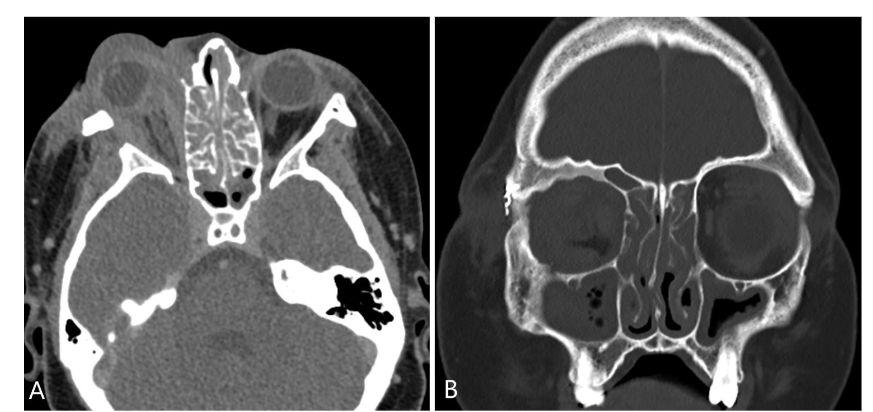

An orbital CT scan showed severe right orbital proptosis, right-sided pre- and post-septal soft tissue thickening with intraconal/retrobulbar space extension and diffuse thickening of the adjacent bone secondary to chronic inflammation without erosion. There was also diffuse paranasal sinus mucosal thickening.